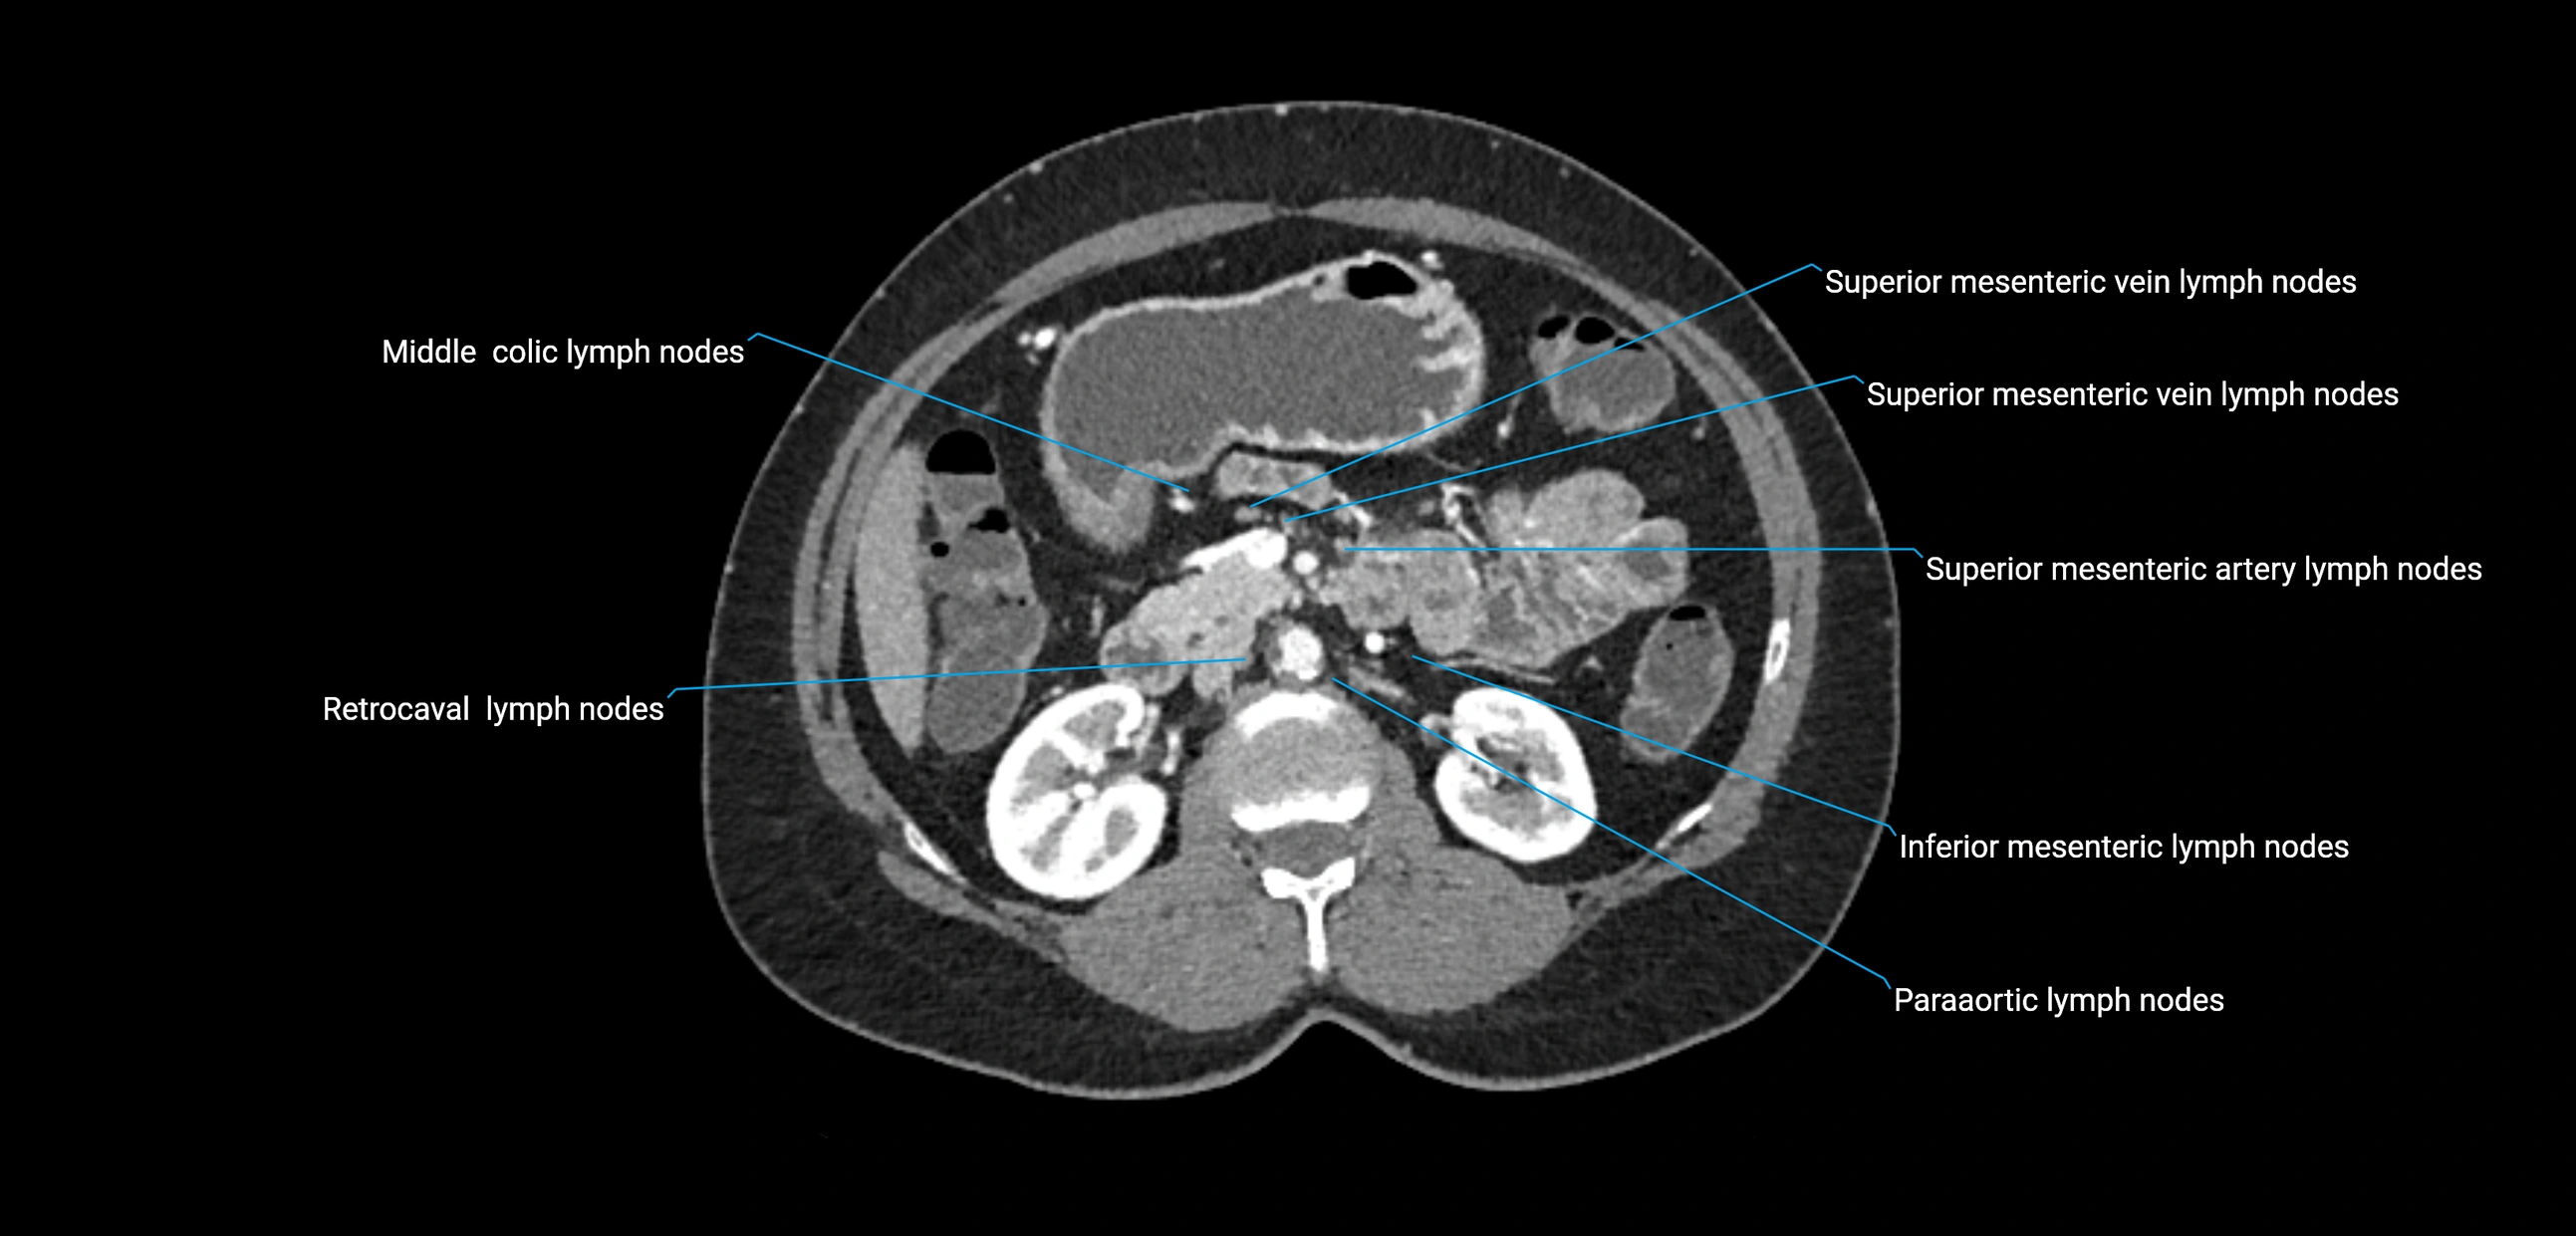

CT Appearance

CT Pre-Contrast:

• Nodes appear as soft-tissue density nodules adjacent to the aorta and IVC

• Calcification may be seen in chronic infections (e.g., tuberculosis)

CT Post-Contrast:

• Normal nodes enhance homogeneously

• Malignant nodes may show heterogeneous enhancement, central necrosis, or conglomerate formation

• Size >1 cm short axis is suspicious, though morphology and distribution are equally important